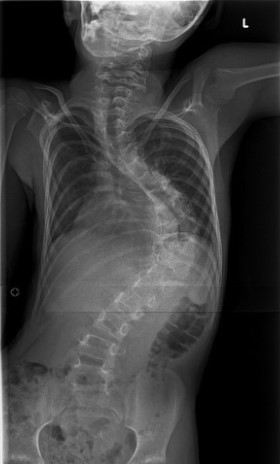

الجنف هو حالة بنيوية تصيب العمود الفقري، حيث ينحني العمود الفقري بشكل غير طبيعي من جانب إلى آخر، وغالبًا ما يصاحبه دوران حول محوره بدلًا من بقائه مستقيمًا عند النظر إليه من الخلف. وقد يأخذ هذا الانحناء شكل حرف S أو C، ويظهر الجنف بشكل أكثر شيوعًا خلال فترات النمو السريع مثل مرحلة المراهقة، إلا أنه قد يحدث في أي عمر.

في العمود الفقري السليم، تُشكِّل الفقرات عمودًا رأسيًا مع انحناءات طبيعية خفيفة من الأمام إلى الخلف. أمّا في حالة الجنف، فإن العمود الفقري ينحني أيضًا بشكل جانبي في المستوى الأمامي، وقد يصاحبه دوران، مما قد يؤدي إلى عدم التناسق في وضعية الجسم والمظهر العام.

ويُؤخَذ تشخيص الجنف عادةً بعين الاعتبار عندما يتجاوز انحناء العمود الفقري حدًا معيّنًا في الفحوصات التصويرية، وغالبًا ما يتم قياس ذلك باستخدام زاوية كوب (Cobb angle) في صور الأشعة السينية.

يبدأ تشخيص الجنف بتقييم سريري يشمل أخذ تاريخ صحي مفصّل وفحصًا بدنيًا شاملًا. وقد يلاحظ الممارس الصحي وجود عدم تماثل في مستوى الكتفين أو الوركين أو الخصر، أو اختلافًا في وضعية الجسم. وتُستخدم الفحوصات التصويرية، مثل الأشعة السينية، لتأكيد وجود الانحناء وقياس درجة شدّته.

في كثير من الحالات، يبقى الجنف الخفيف مستقرًا ولا يسبب أعراضًا ملحوظة. ومع ذلك، فإن الانحناءات التي تتفاقم بمرور الوقت — خاصة خلال فترات النمو السريع — قد تؤثر على وضعية الجسم، والقدرة على الحركة، ومستوى الراحة. أما الانحناءات الشديدة، فقد تؤثر على الوظيفة الميكانيكية للعمود الفقري والأنسجة المحيطة به إذا لم تتم متابعتها وإدارتها بشكل مناسب.